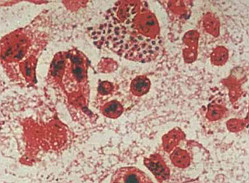

三、病理改变

皮肤黏膜念珠菌病常见组织出现红肿、糜烂、溃疡等病变;内脏念珠菌病则有脏器出现脓肿性或肉芽肿病变。脓肿内可见芽孢和菌丝。

怀疑有念珠菌食管炎的患者,则不仅应做内镜刷取标本检查,同时应做活检,以进一步从组织病理学查找念珠菌侵袭黏膜的证据。 深部念珠菌的组织反应不具特征性。一般呈急性化脓或坏死,可有多个脓肿或微小脓肿,内含大量中性粒细胞、假菌丝和芽胞。组织中的假菌丝和芽胞是深部念珠菌病的确诊证据。